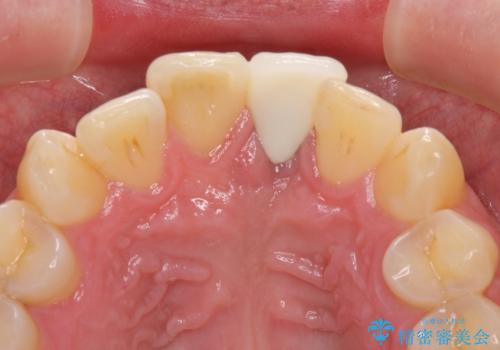

インプラントが唇側に埋入されており、セラミッククラウンの歯肉ラインが左右非対称となっていました。

仮歯は両サイドの歯と接着剤で止められており、接着が著しく変色していたため、セラミッククラウンが装着されて自然な口元となりました。